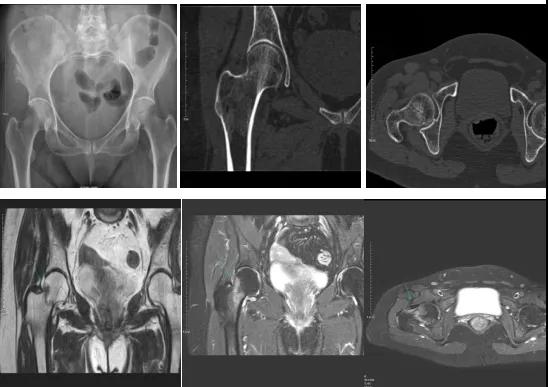

DR示:右側(cè)股骨頸未見明顯骨折征象。CT右側(cè)股骨頸骨質(zhì)密度不均?;颊唧w征明顯,為明確診斷,行MRI檢查。MRI示:右側(cè)股骨頸T1WI呈低信號,脂肪抑制序列呈高信號;提示右側(cè)股骨頸隱匿性骨折。

2.CT或MRI檢查。CT是斷面成像,不會出現(xiàn)重疊而導(dǎo)致漏診,同時CT還可以進行多平面的重建,除了發(fā)現(xiàn)X線無法發(fā)現(xiàn)的骨折外,還可以三維直觀的顯示骨折的程度,對臨床治療有指導(dǎo)意義。CT無法發(fā)現(xiàn)骨裂、不全骨折或者骨挫傷,對軟組織的損傷診斷也有局限性,MRI就可以發(fā)現(xiàn)這些損傷。

一般骨科創(chuàng)傷的病人,只要到影像科拍一張X光片,很快就會明確診斷有沒有骨折。然而有一些特殊類型骨折的病人,由于拍片影像重疊的緣故,或者骨折未發(fā)生明顯移位,病變可能顯示不出來,等過了一段時間后,骨折部位才能夠顯示清楚。這種類型的骨折,叫做隱匿性骨折。若在臨床上診斷及時且明確,及時固定患者的骨折部位,進行適當(dāng)治療并減少運動,對患者的恢復(fù)有重要意義。